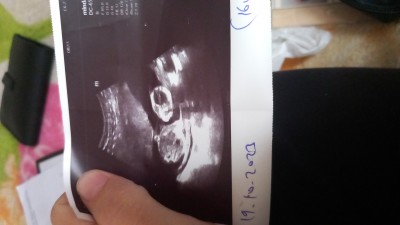

12 haftalıkken doktor erkek dedi özelde sonra 15 haftalıkken devlete  gittim bacakları kapalı kız olabilir dedi  16+5 özele gittim erkeğe benziyor dedi çok merak ediyorum ya

Bişey görmedim ben daha net yok mu kesesi falan belli olan bı fotoğraf

Zaten görünen yer bacak arası

Bence erkek